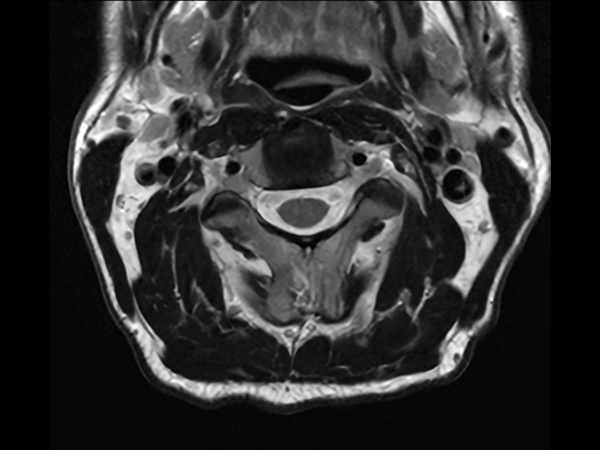

High quality Cervical Spine imaging with SmartSpeed Precise